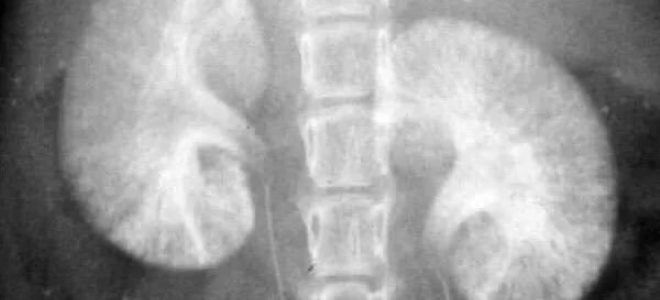

Дополнительно могут быть назначены рентгенологические исследования, такие как экскреторная урография, которая позволяет оценить функцию почек и их анатомические особенности. Этот метод включает введение контрастного вещества, что помогает визуализировать мочевыводящие пути и выявить возможные аномалии.